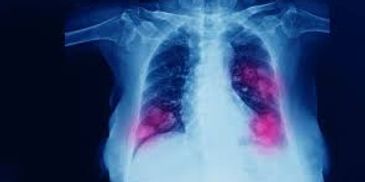

Over two-thirds of all people know someone who has cancer. This course provides students with a more extensive understanding of what cancer is and how it affects the human body. We will discuss the history of cancer research, the many different types of human cancers, and basic chemotherapeutics. The topics will be presented in a basic scientific nature with an emphasis on gaining a broad understanding of the subjects. Prerequisite: Biol 2960 or equivalent. Not available to students who have credit for Biol 144 or Biol 1440.

This advanced course provides students with a more in-depth understanding of the molecular mechanisms of cancer. We will discuss tumor suppressors, oncogenes, signaling pathways, animal models in cancer, and novel targeted cancer therapies being developed by biotechnology and pharmaceutical companies. Prerequisite: Biol 144, Biol 1440 or Biol 4715.